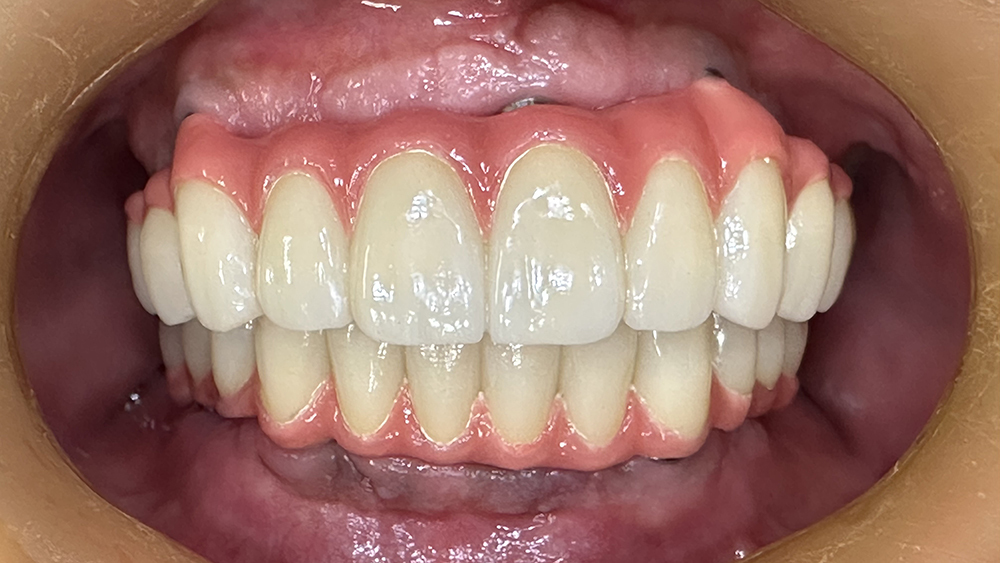

症例3

Before

After

MHさん、84歳女性

非喫煙者

治療の期間・回数:約6か月

​治療の価格:約2,200,000円

治療内容:当院では平成5年から上あごの「オールオンX」を行っていますが、この方は最も古い患者さんです。

すでに21年経過しています。右下の歯が折れたため、12年前にオステムインプラントを1本追加しました。